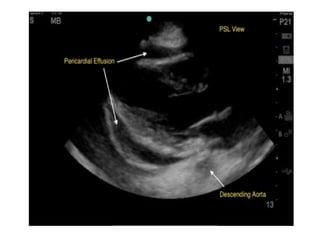

Scans are obtained at 4 interfaces:

•Pericardial sac

•Hepatorenal interface

•Splenorenal interface

•Pelvis interface

Pericardial interface